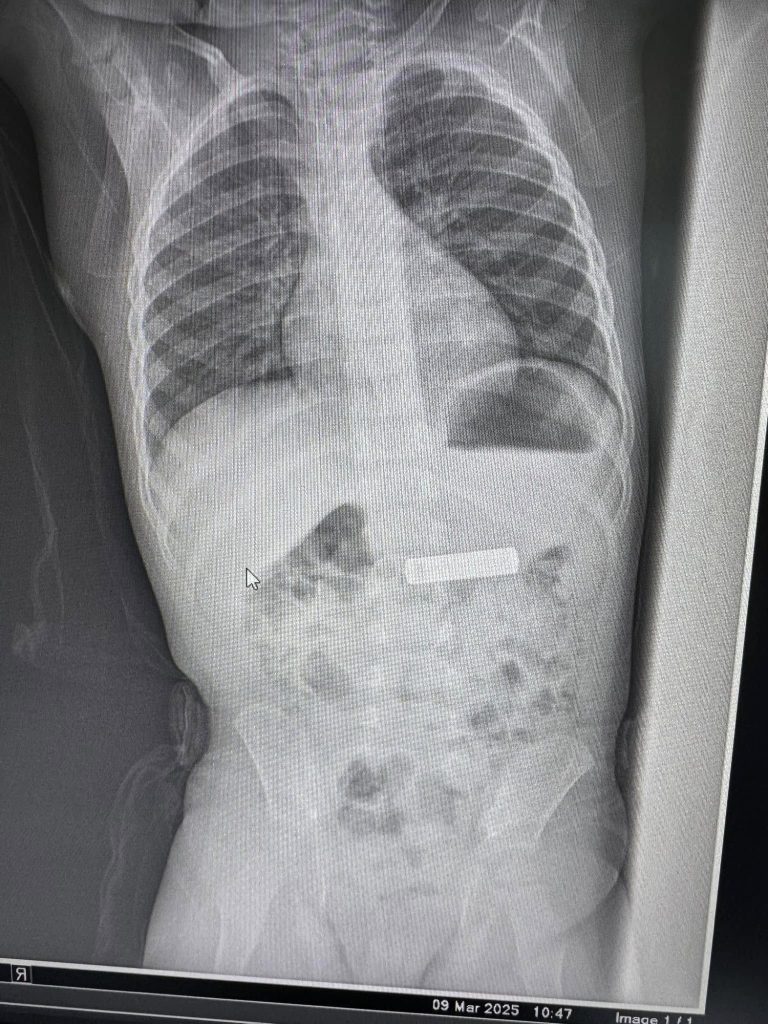

Gastroenterologu Besnik Elezi ia ka hequr nga barku baterinë “Varta” një fëmije 2-vjeç.

Elezi këtë rast e ka publikuar në faqen e tij në Facebook. Fëmija është trajtuar në ordinancën e Elezit.

“Largohet nga stomaku baterie e telekomandes te femija 2 vjet K.Sh”, ka shkruar Elezi.

Më poshtë mund t’i shihni fotografitë që i ka publikuar vet Elezi.